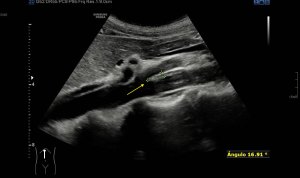

Los vientres anteriores de los Músculos Digástricos derecho e izquierdo forman los bordes laterales del triángulo submentoniano, mira:

En este triángulo lo que vas a encontrar son ganglios.